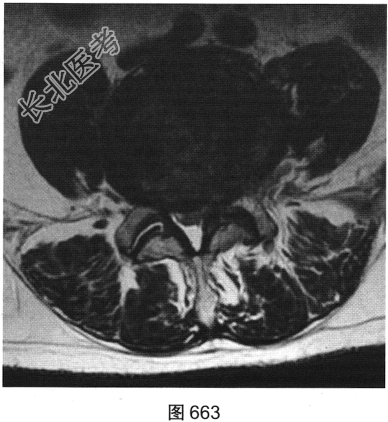

- 多项选择题3.[提示]患者行腰椎MRI检查,如图660~图663所示。患者MRI的T2压脂像上, 部分椎体上、下缘高信号提示( )

- 多项选择题4.综合X线、CT和MRI图像,该患者有以下哪些腰椎退变征象( )

A、终板炎

B、腰椎间盘突出

C、许莫结节

D、黄韧带肥厚

E、腰椎管狭窄

F、腰椎间盘脱出,髓核游离